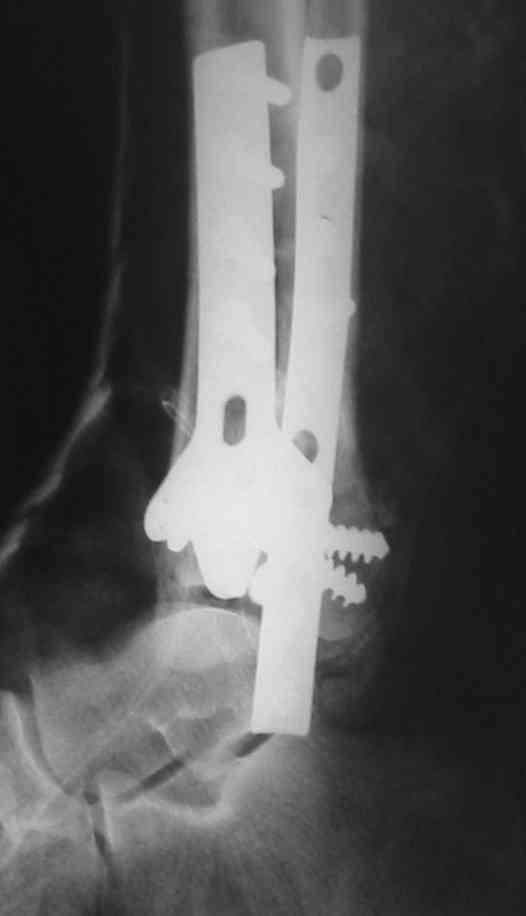

OK, Dr Driagin, Ja operiroval bolnogo po Vashemu, hotia sam ni ochen' ubezden' v itom, t.k. bolnoi otkazalsa na proch' ot ex.fix, ja emu sdelal ORIF + Kostnia plastika, snimky prelogiottsa,

Очень прилично получилось, но мне показалось, что винты на 4,5 мм.Это принципиально винты используются 3,5 и 4,0 мм. И проекцию прямую бы переделать. С уважением Дрягин

На представленном снимке видно, что эпифиз смещен латерально.

Сейчас с этим ничего не сделать, похоже.

Однозначно сказать сложно.Расстояние между тараном и медиальной лодыжкой меньше чем между тараном и крышей большеберцовой кости.Это может быть за счёт не правильной укладки.Пока не отчаиваетесь.Главное вы поняли принцип.Сделайте несколько проекций прямых и посмотрим.Для всех интересно.С уважением

Мне кажется, что все конечно далеко от идеала. Сложный перелом. Есть ощущение, что малоберцовая кость (ключ!) фиксирована с ротацией и удлинением. Снимки конечно необходимо сделать в правильных проекциях и без гипса...

В голеностопном суставе обязательны 3 стандартные ренгенологические проекции: прямая, латеральная и мортиз. Без них невозможно трактовать состояние голеностопа.

Применение шурурпов 4.5 мм и более толстых пластин крайне недопустимы. Рекомендуется низкопрофильные, контурированные пластины с шурупами 3.5 мм, а иногда те же 3.5 шурупы но с головкой 2.7 мм.